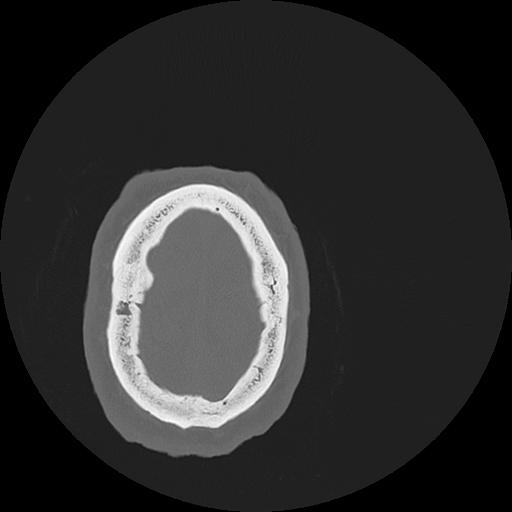

7 HUESO,,Vol,0.5,HUESO,,